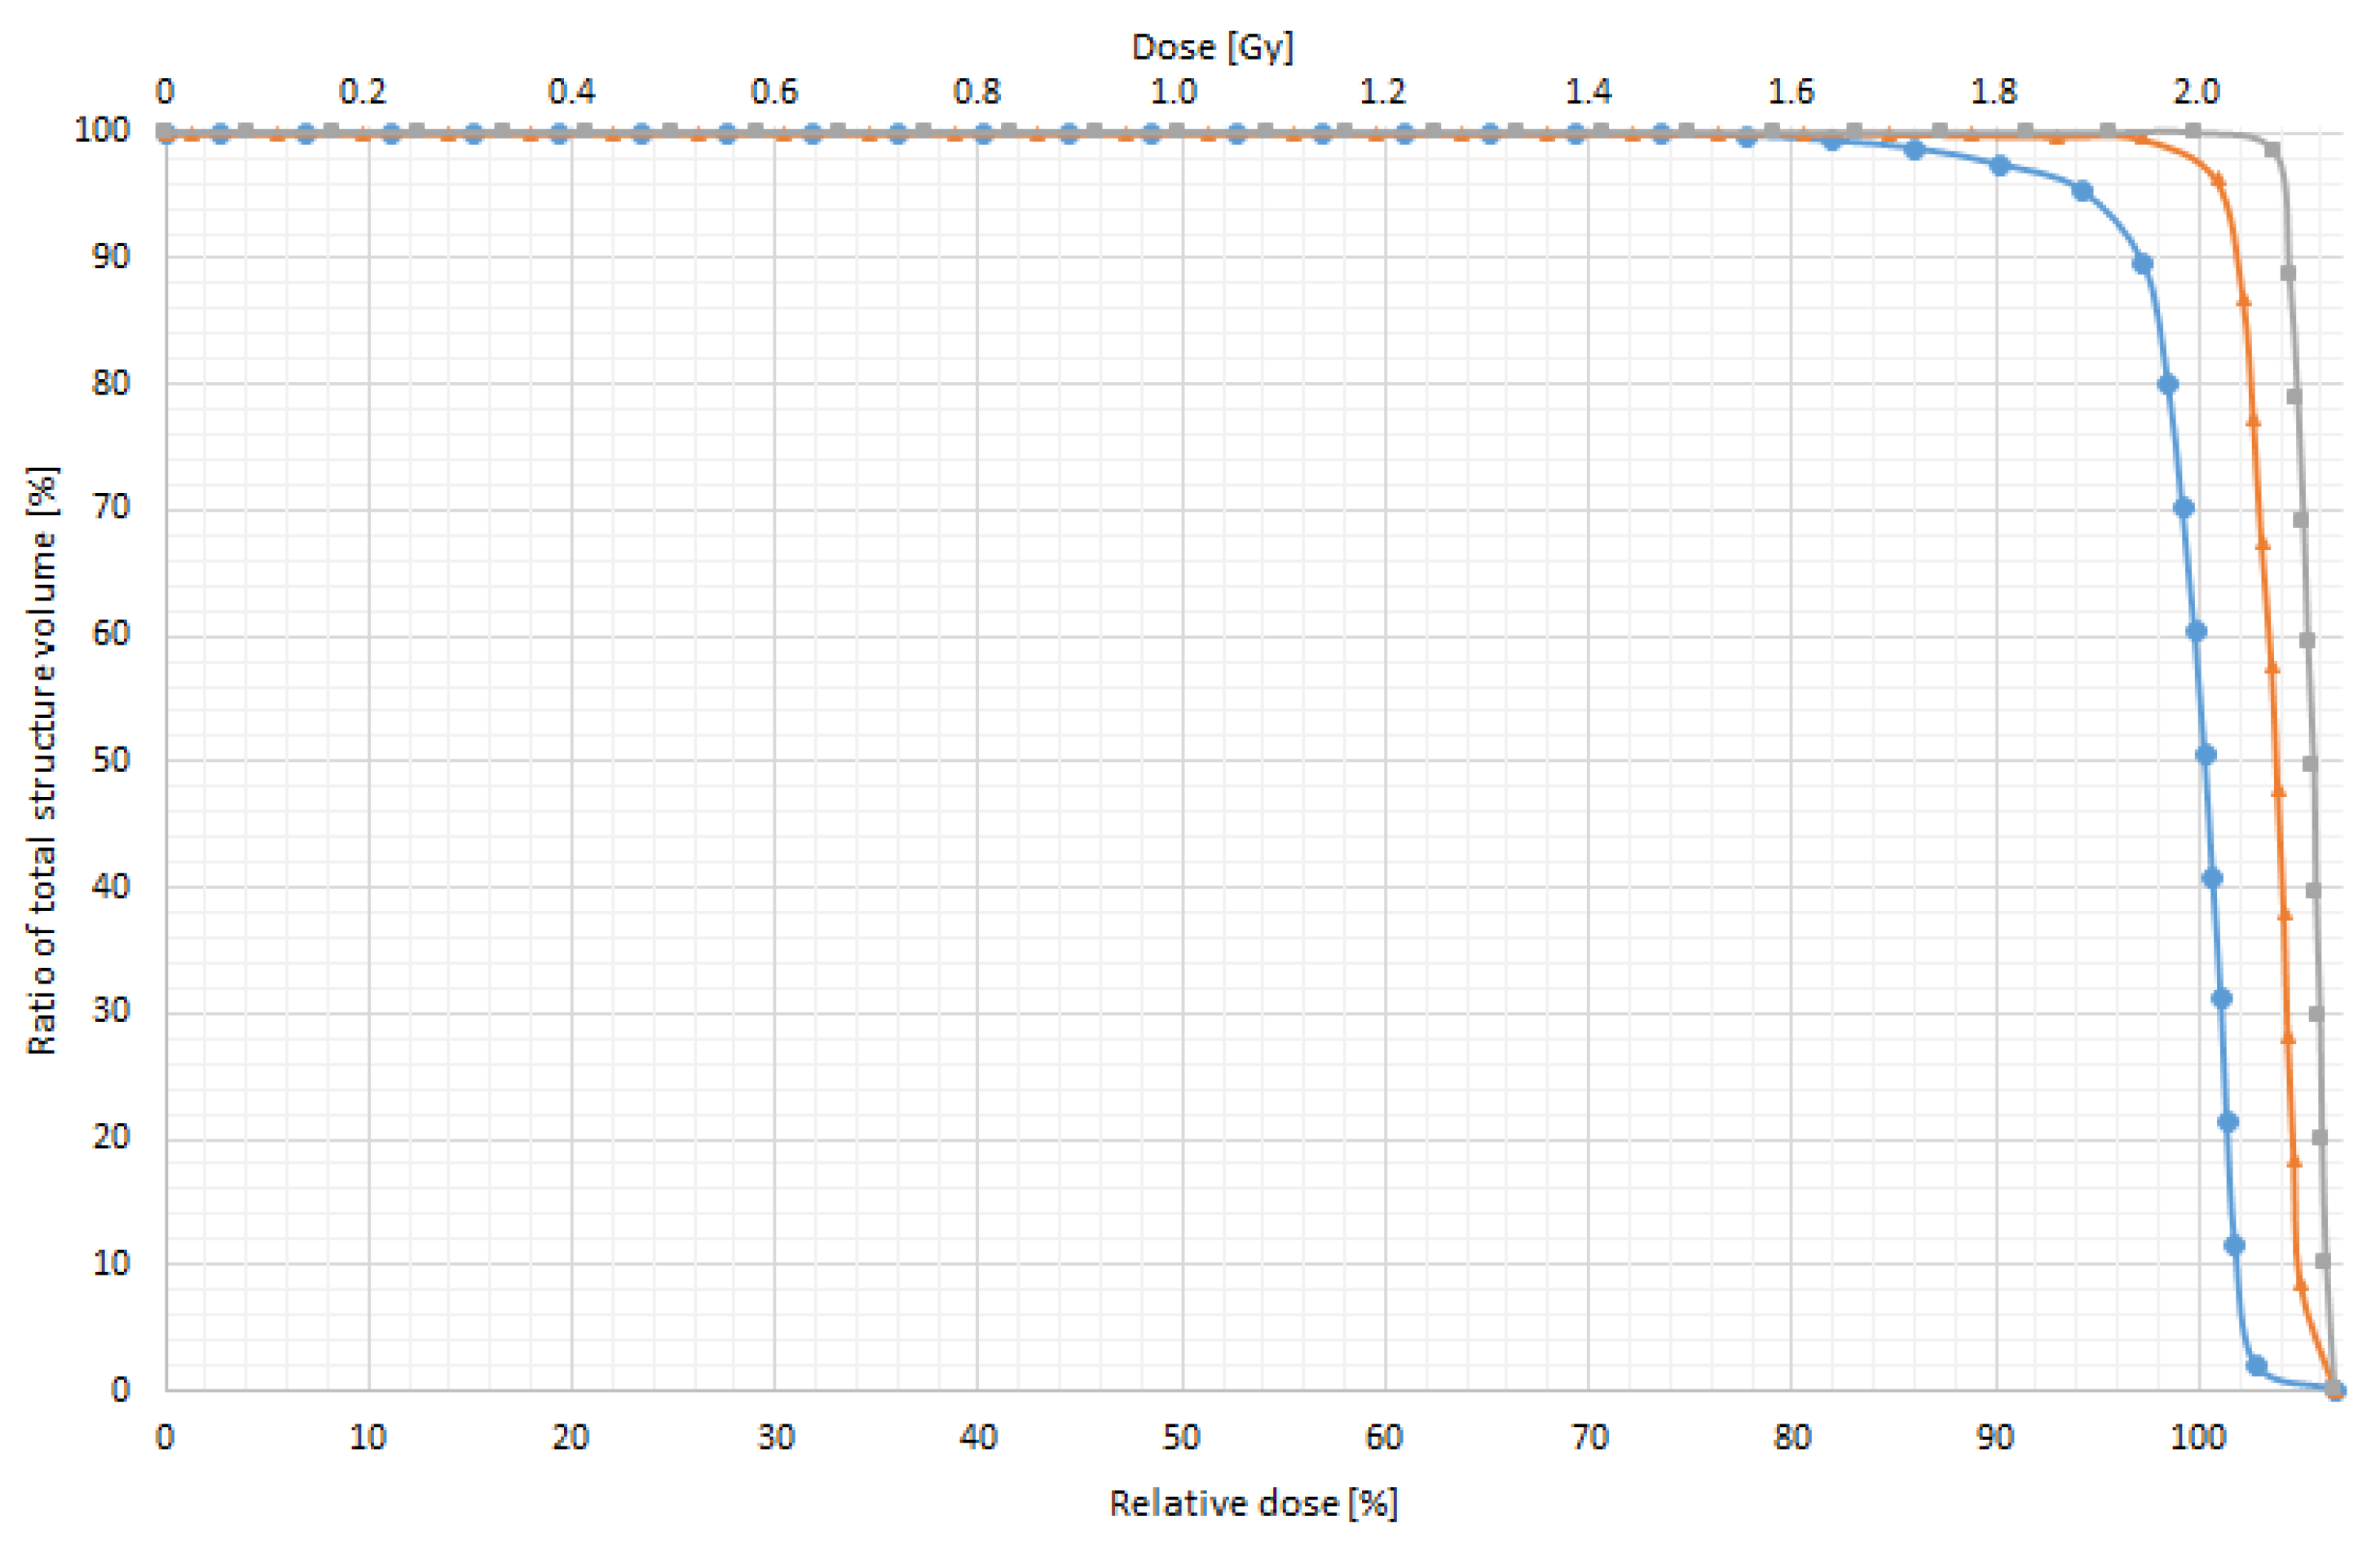

| A Single-Field Plan | Difference from Prescribed Dose 2 Gy | |||||

|---|---|---|---|---|---|---|

| D95% | D97% | D99% | ||||

| Gy | % | Gy | % | Gy | % | |

| Without bolus | 0.85 | 40.0 | 0.98 | 50.0 | 1.04 | 52.0 |

| With 0.5 cm bolus | 0.01 | 0.5 | 0.04 | 2.0 | 0.06 | 3.0 |

| With 1.0 cm bolus | 0.00 | 0.0 | 0.01 | 0.5 | 0.03 | 1.5 |

| IMRT Plan | Difference from Prescribed Dose 2 Gy | |||||

|---|---|---|---|---|---|---|

| D95% | D97% | D99% | ||||

| Gy | % | Gy | % | Gy | % | |

| Without bolus | 0.1 | 5.14 | 0.17 | 8.64 | 0.52 | 26.04 |

| With 0.5 cm bolus | 0.007 | 0.35 | 0.008 | 0.4 | 0.02 | 0.98 |

| With 1.0 cm bolus | 0 | 0 | 0 | 0 | 0 | 0 |